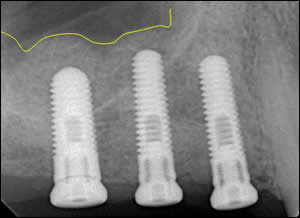

Fig 3: Post-operative radiographs reveals placement of 3 dental implants after “non-surgical” sinus elevation.

Fig 4: Tracing of the repositioned sinus floor providing ample space for 3 dental implants.